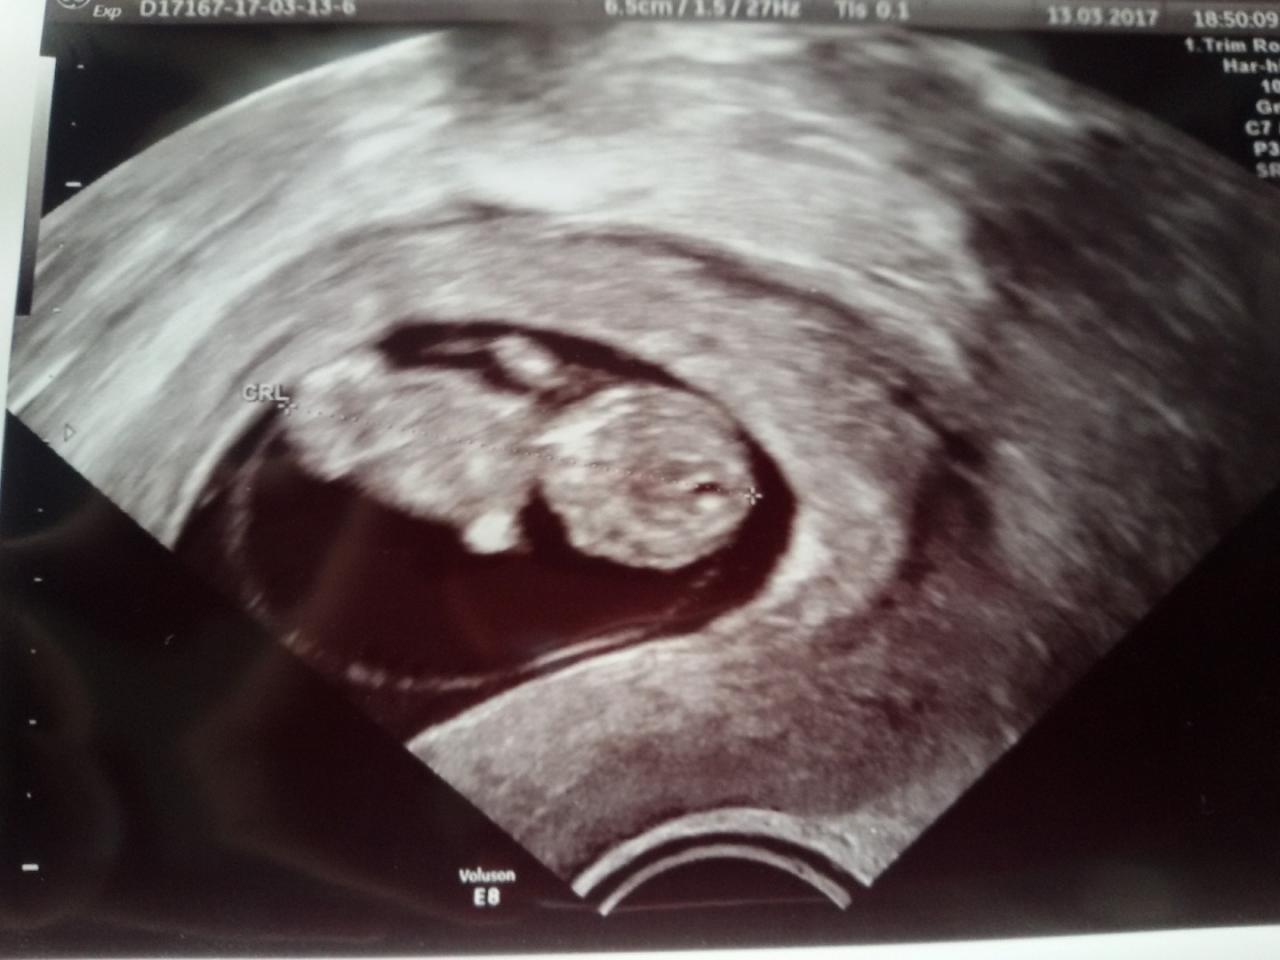

Ja juz po wizycie [emoji4] dzidziuś w stadium Gumisia. Ma 2 cm. Dobry sprzęt, wiec było super widać jak bije serduszko.

Pobrali mi tez chyba 10 litrów krwi na wszelkie badania. Usg genetyczne mam za 3 tyg. [emoji4] bardzo jestem zadowolona. Termin tez narazie zostaje na 16.10. Jeszcze ktoś w tym terminie?

I sweet focia: